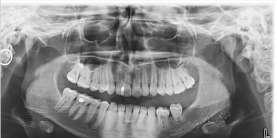

Hon föreläste om resultatet av sitt examensarbete, där hon jämfört tandläkarhögskolans tidigare och nya röntgenapparaters bildkvalitet.

– Vi hade två parallella grupper, ena tittade på bildkvaliteten och min grupp specifikt på avskärmningar, säger Mathilde.

Resultatet kommer förmodligen att användas av tandläkarhögskolan i framtiden.

– Det blev lite sämre med den nya röntgenutrustningen Signifikant, men inte enormt mycket Framför allt var det intressant att se vissa mönster där risken för fel är större

Det i sin tur kan leda till att utbildningen formas om, menar Mathilde

– Så även om resultatet blev sämre bildkvalitet, är det trots det en kunskapsvinst för skolan.